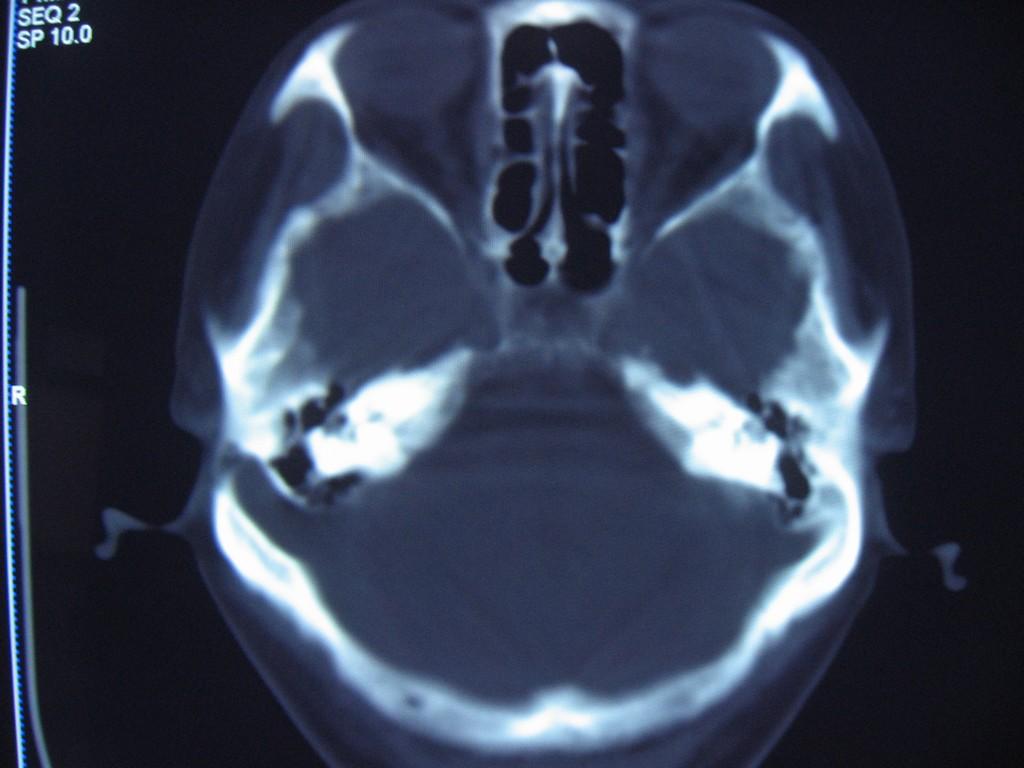

中老年女性病人,头晕头疼做ct,发现右侧乙状窦路径上低密度影,邻近颅骨变薄,ct值见图像上标注,我考虑:1、表皮样囊肿或蛛网膜囊肿。2、乙状窦变异。请问对吗?  乳突导静脉没有考虑,主要是因为向颅底层面扫了几层没有发现右侧颞枕骨骨质完整,没有发现导静脉压迹,欢迎讨论。

1)右侧乙状窦前移。2)右侧乙状窦区皮样囊肿或表皮样囊肿待排;建议行mri检查。

右侧乙状窦前移。2)右侧乙状窦区皮样囊肿或表皮样囊肿